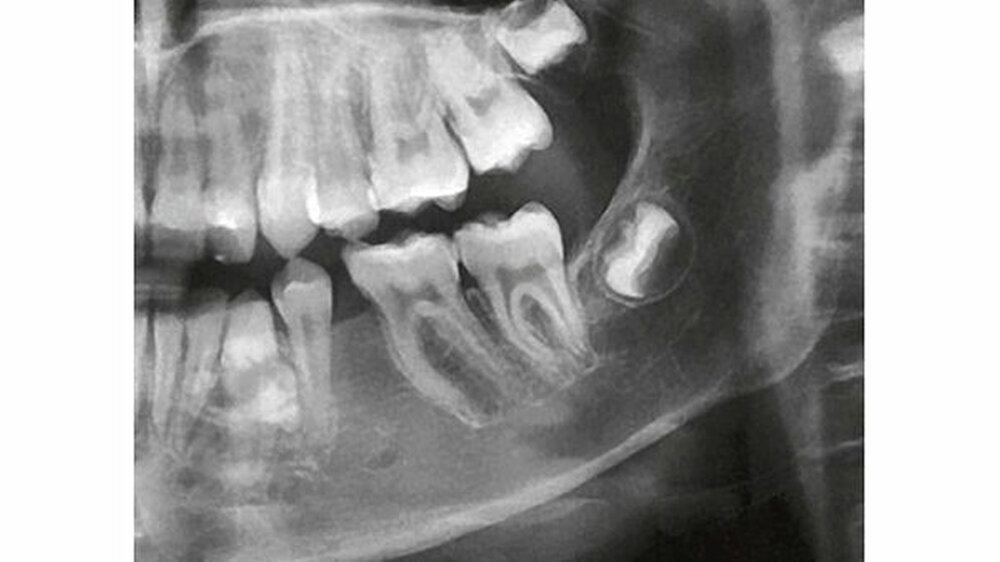

Auf dem mitgelieferten vier Jahre zuvor erstellten Orthopantomogramm (OPT) waren noch keine Hinweise auf das Vorhandensein einer Veränderung regio 32-34 sichtbar (Abbildung 2). Ein Jahr später konnte anhand des OPT bereits eine radioopake Struktur regio 33, 34 festgestellt werden (Abbildung 3). Auf dem aktuellen OPT und digitalen Volumentomogramm (DVT) zeigten sich regio 32-34 lingual multiple, rundliche, unterschiedlich große Radioopazitäten, umgeben von einer radioluzenten Zone.